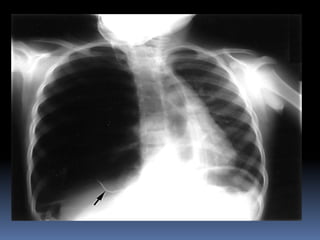

Abnormal Findings Un equalityof chest movement Hyper resonance on percussion Decrease air entry Tachypenic Pneumo thorax chest tube

Pneumo thorax

chest tube

A simple pneumothorax can be converted to a tension

pneumothorax when a patient is intubated and

positive pressure ventilation is provided before

decompressing the pneumothorax with a chest tube.